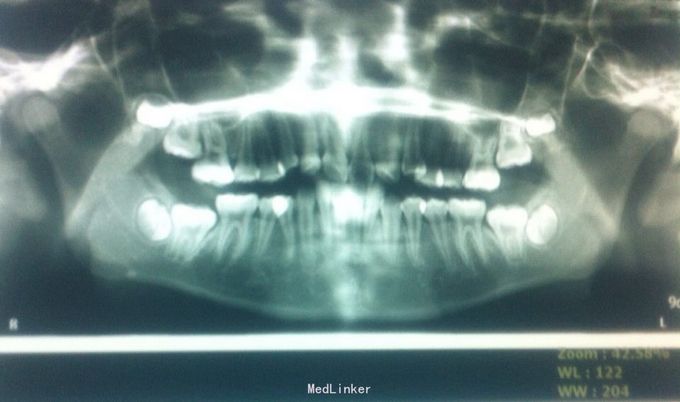

恒牙期 33,44唇侧错位 磨牙中性关系 前牙覆合2度、覆盖1度 牙列拥挤

牙列拥挤、安氏一类 拔牙矫治,拔除14、24、34、44(强支抗)排齐整平上下牙列,直丝弓矫治器,关闭拔牙间隙,矫治后前牙覆合覆盖正常,磨牙中性关系,面型略改善

18.28.38.48牙胚存在,必要时拔除